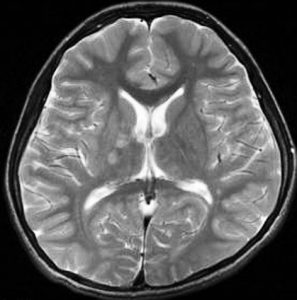

germinomaの視床浸潤:ミッキーマウスの耳

松果体ジャーミノーマは両側視床に浸潤して視床浮腫を生じます。真ん中に第3脳室後半部の割れ目が残っているのが特徴的な所見です。ミッキーマウスの耳みたいになります。かなり特異的な所見であり診断に有用です。右下は治療後です。